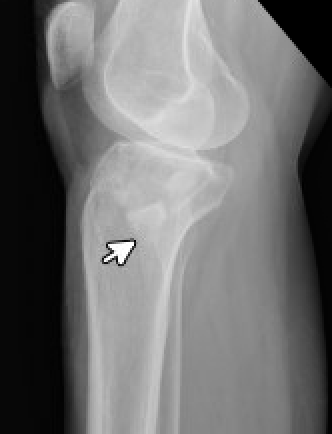

This xray is the lateral projection of the film directly above this one. The fracture and displacement of the tibial plateau is more appreciable in this view.